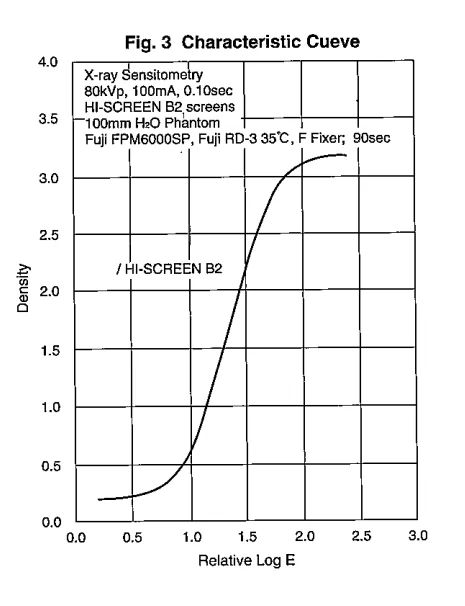

This film is designed for 90-seconds automated processing or manual processing.

The former is recommended with any kinds of film processor, developing at 30-35 in 23s.